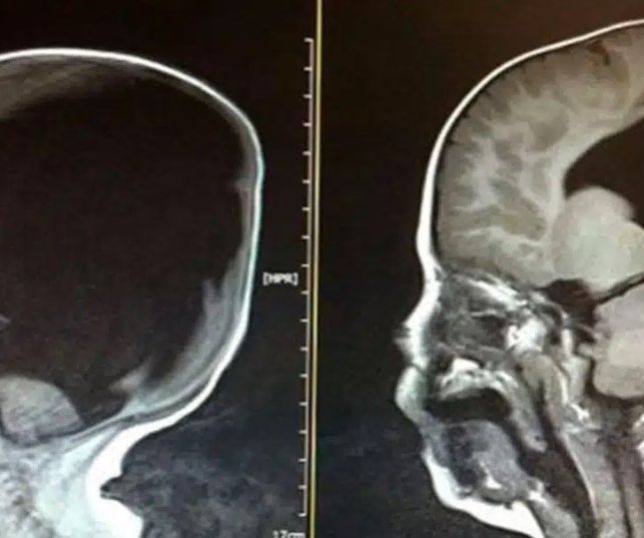

Exame revelou que um universitário não tinha cérebro. Sua cabeça estava cheia de água